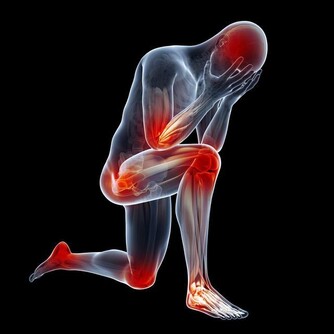

4、手腳發麻、冰涼

當身體中血糖過高時,血液中血糖濃度就會增加,導致了血液粘稠,影響了血流速度,而血液循環受到影響,我們的手腳就會遭殃。

從而出現手腳發涼、足底發緊、感覺異常等等,尤其在夜間更明顯。